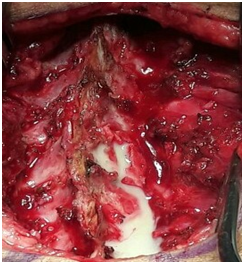

It is a 15-month-old infant of Mauritanian nationality, with a history of unprotected neonatal infection, received in our neurological clinic for motor deficiency of the two lower limbs. His psychomotor development was normal. The symptomatology evolved for about 4months, with the occurrence of a fever, irritability and a dorsal kyphosis. In view of these manifestations, the infant was brought to the local health center for treatment, where a non-documented treatment has been instituted for a period of 10days. After 10days of treatment, the patient presented progressively over 20days a motor deficit of the lower limbs preceded by a functional impotence of the lower limbs causing an impossibility of the walking and the seated station, without context of acute retention of urine or constipation. This is what motivated the parents to consult again in another health center in Nouakchott where the patient was hospitalized for 5days and left without improvement of his clinical picture. Finally, he will be referred to the FANN Neurology Clinic in Dakar for specialized care. It should be noted that the parents of the infant had detected a dorsal cutaneous swelling during his neonatal period, but they had thought that it was an innocent lesion that did not need further investigation (of little clinical importance). The clinical examination found a good state of hydration, hyperthermia at 38.5°C. The infant was conscious with good preservation of superior functions. However, he had a spastic paraplegia with a muscular force rated at 0/5 on the two lower limbs, osteo-tendinous reflexes were sharp at the two lower limbs, poly kinetic and diffuse with an epileptoid trepidation of the feet, plantar reflexes were in extension, the neck was supple. On the other hand, tone, muscle strength and osteo-tendinous reflex were normal to the upper limbs. There were no signs of meningeal irritation. At the level of the musculoskeletal system, a kyphosis of the dorsal spine was noted with a slight hyper chromic swelling surrounded by a pilosity with respect to the T3-T4 dermatomes, suggesting a dermal sinus (Figure 1). The rest of the clinical examination was normal. The hypotheses of a compressive or non-compressive myelopathy associated with dysraphia were mentioned. The medullar MRI performed showed an edema of the cervico-dorsal marrow as well as the bulbar junction, with lesional signal abnormality, hypo-intense T1, hyper-intense T2, heterogeneous enhancement, with a small area In a cockade with a hypo-intense center at the height of C6-C7, a part strongly raised facing T1 and a fusi form part of 31x11,8mm just below. A linear fistula was seen, communicating the collected lesion to the skin (Figure 2). The diagnosis of intramedullary abscess was retained. The haematological assessment found a leukocytosis at 19000/mm3 and the sedimentation rate was high. A neurosurgical procedure was performed and confirmed the existence of the dermal sinus, communicating the skin to the medullary space through a cord (Figure 3). Partial Laminectomy was performed with drainage and lavage of the cavity (Figure 4), but also a resection of the sinus. The cytobacteriological examination of pus isolated Staphylococcus aureus. Prior to pus culture, treatment consisted of broad spectrum antibiotic therapy with Ceftriaxone, Metronidazole and Gentamycin. And after the isolation of the germ, the infant was put on Vancomycin and Chloramphenicol. Evolution was satisfactory with partial recovery of muscle strength.

Figure 2 This image shows pus evacuated from the medullary space after partial laminectomy.